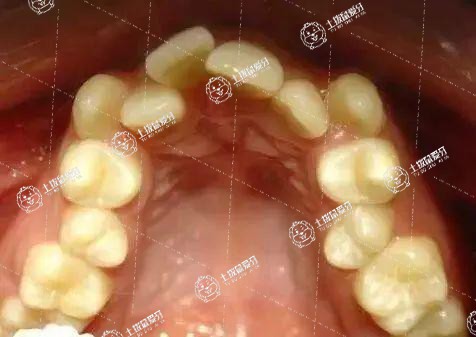

牙列擁擠臨床表現(xiàn)為不對(duì)稱的唇部外突、口腔內(nèi)牙齒參差不齊、咬合不良以及牙周創(chuàng)傷等。牙列擁擠矯正,必須根據(jù)擁擠程度、患者年齡、健康狀況以及面頜發(fā)育、面部肌肉張力等,做出正確矯正方案。

臨床上將牙齒擁擠分為輕度擁擠和重度擁擠兩種。對(duì)輕度牙齒擁擠的矯正,擁擠程度表現(xiàn)為上下切牙扭轉(zhuǎn)錯(cuò)位,或尖牙輕度唇向錯(cuò)位,采用牙套正畸矯正方法。中度和重度擁擠,采用重塑拔牙配合矯正器治療。成年人生長(zhǎng)發(fā)育已經(jīng)完成,代謝速率變慢、生物反應(yīng)性降低,采用正畸矯正成人牙列擁擠或比兒童所花時(shí)間更長(zhǎng)些。牙列擁擠可通過拔牙或不拔牙方式進(jìn)行矯正。